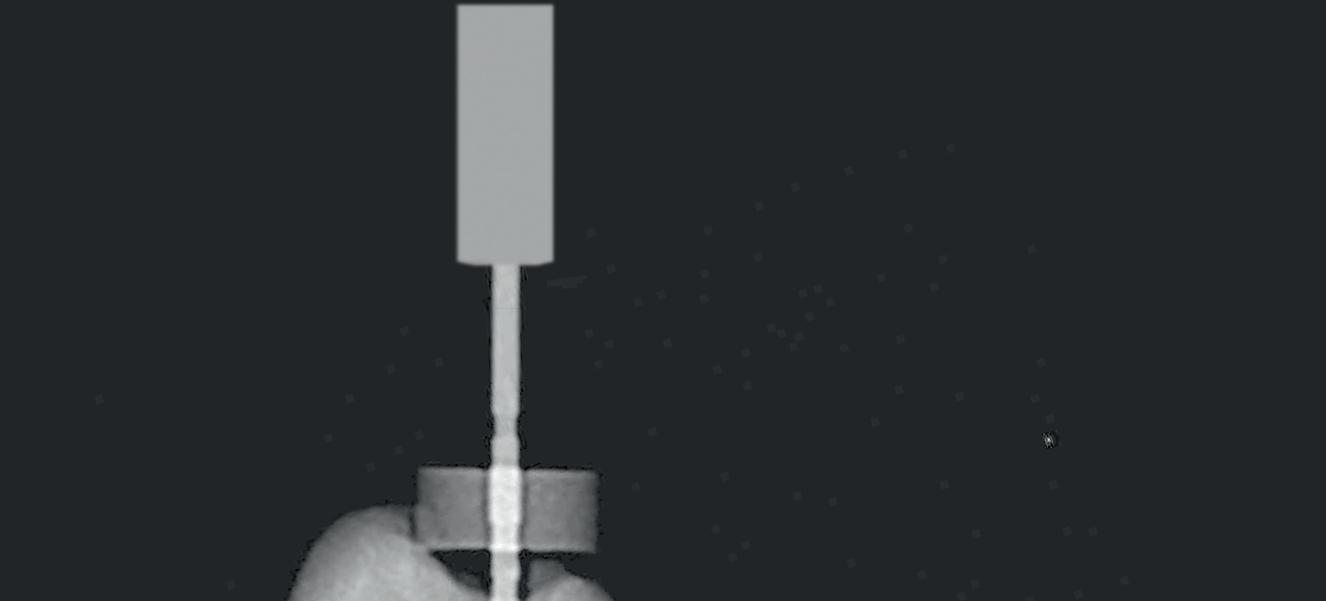

Tri Auto ZX2+

CCW CW CW CCW File example Mode Sequence CW CCW 3